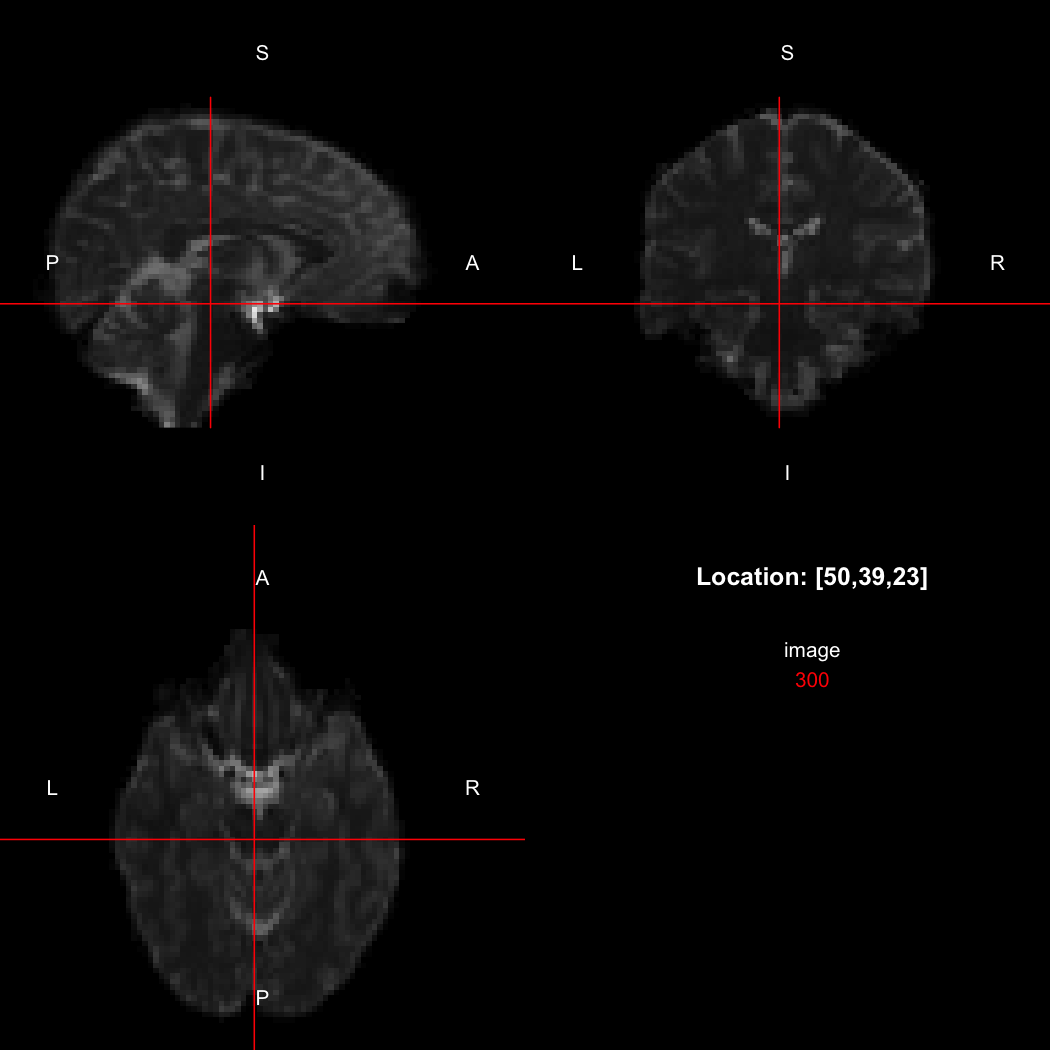

image <- readNifti(system.file("extdata", "example.nii.gz", package="RNifti"))We can also use the RNifti image viewer to visualise the

image.

view(image)